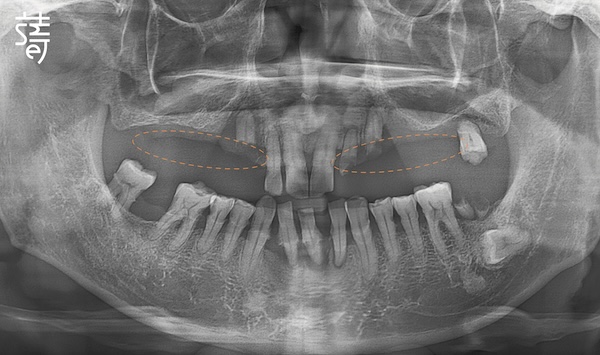

像黃爸爸這樣的嚴重骨質流失,不僅需要五支,

更得藉助顴骨植體來強化支撐,

才能確保長久穩固。

錢醫師進一步說明,這正是顴骨植體發揮關鍵作用的原因。

黃爸爸能順利完成重建,靠的就是其中兩根顴骨植體。

此技術專為嚴重缺骨患者設計,特別適合上顎骨幾乎全數流失、傳統方式已無法重建的情況。

顴骨位於眼眶下方外側,骨質緻密且穩定,不易隨時間吸收。

This is where zygomatic implants play a decisive role. Designed specifically for patients with extreme bone loss, They anchor into the dense cheekbone located on the outer side just beneath the eye socket—a bone that remains stable and resists resorption over time.

即便上顎骨基底幾乎完全流失,將植體直接固定於強壯的顴骨,仍能建立牢固的支撐。

不僅穩固,還能免去大範圍補骨與漫長等待,為重建帶來突破性的解方。

Even when the upper jawbone is almost completely gone, zygomatic implants can provide the firm foundation needed, eliminating the need for extensive bone grafting and long recovery delays. For Mr. Huang, two zygomatic implants made his reconstruction possible.

不過,顴骨植牙屬於技術門檻極高的手術,植體需穿越萎縮的上顎骨,固定在堅硬的顴骨。

長達 30~52mm 的植體比傳統更長,雖然支撐力更強,但對醫師操作的精準度要求極高。

Zygomatic implants are considered one of the most technically demanding procedures in implant dentistry. The implant, often measuring 30 to 52 mm, must traverse the resorbed maxillary bone and anchor securely into the dense zygomatic bone. While this provides strong and stable support, it also requires an exceptional level of surgical precision and anatomical understanding.

不同於一般診所僅拍攝局部影像,蒔美採用高階全頭顱 CT 掃描,

完整呈現從頭頂到下巴的顏面立體結構,確保醫師能精準避開所有風險區域。